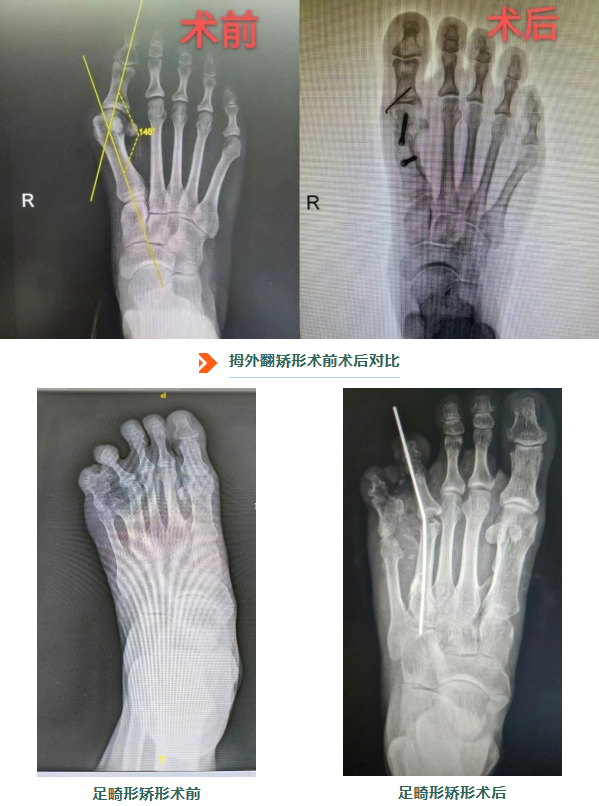

2、足踝畸形矫形:告别疼痛

开展各类先天性与获得性足踝畸形的矫形手术,如拇外翻、扁平足、高弓足、马蹄内翻足等。团队运用生物力学原理,通过截骨、肌腱转位、关节融合等精细操作,不仅矫正外观畸形,更着力恢复足部的生物力学平衡与行走功能,帮助患者告别疼痛。